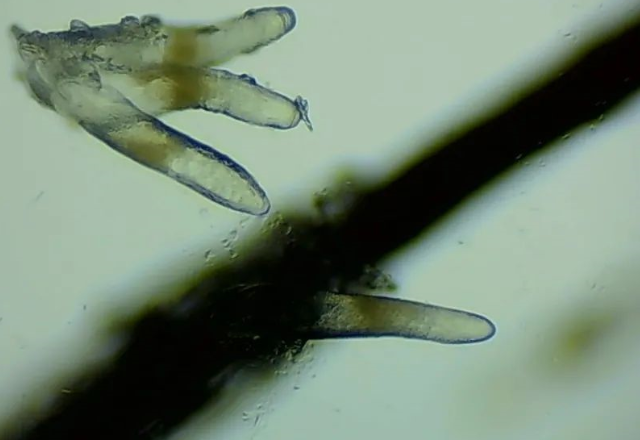

47歲的楊阿姨,近一個(gè)月來(lái)眼睛又干又癢,時(shí)不時(shí)流眼淚,一揉眼睛還有很多睫毛掉下來(lái),為了查明病因,她趕忙來(lái)到廈門(mén)眼科中心就診。結(jié)果出人意料,顯微鏡下,楊阿姨睫毛上竟然寄居著不少“小蟲(chóng)”,最多的有10多條?。?!

▲顯微鏡下,睫毛上的螨蟲(chóng),它們長(zhǎng)著透明膠狀的身體,揮舞著爪子。

原來(lái),顧女士眼部奇癢,是因?yàn)樗腥玖巳湫悟?。?dāng)寄居的蠕形螨達(dá)到一定的數(shù)量,便引起了蠕形螨感染性瞼緣炎。

廈門(mén)眼科中心的醫(yī)生介紹,在門(mén)診中,這樣的病例并不少見(jiàn)。人體螨蟲(chóng)主要有兩種,一種是皮脂螨,主要寄生于皮脂腺和瞼板腺內(nèi);另一種是蠕形螨,“住”在睫毛毛囊里,晚上從毛囊里爬出來(lái),白天躲在毛囊里產(chǎn)卵。